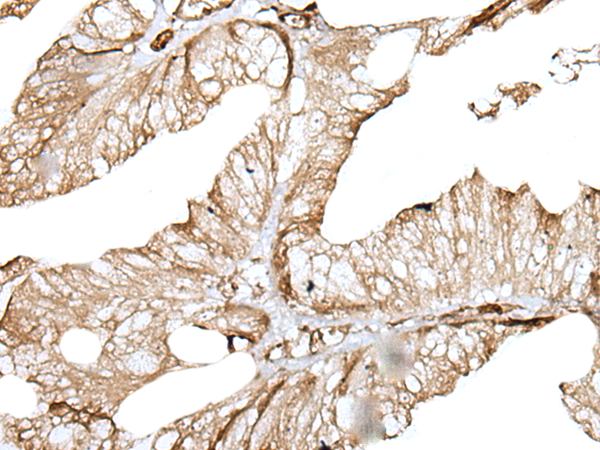

IHC (Immunohiostchemistry)

(The image on the left is immunohistochemistry of paraffin-embedded Human lung cancer tissue using ZNF496 Antibody at dilution 1/30, on the right is treated with fusion protein. (Original magnification: x200))